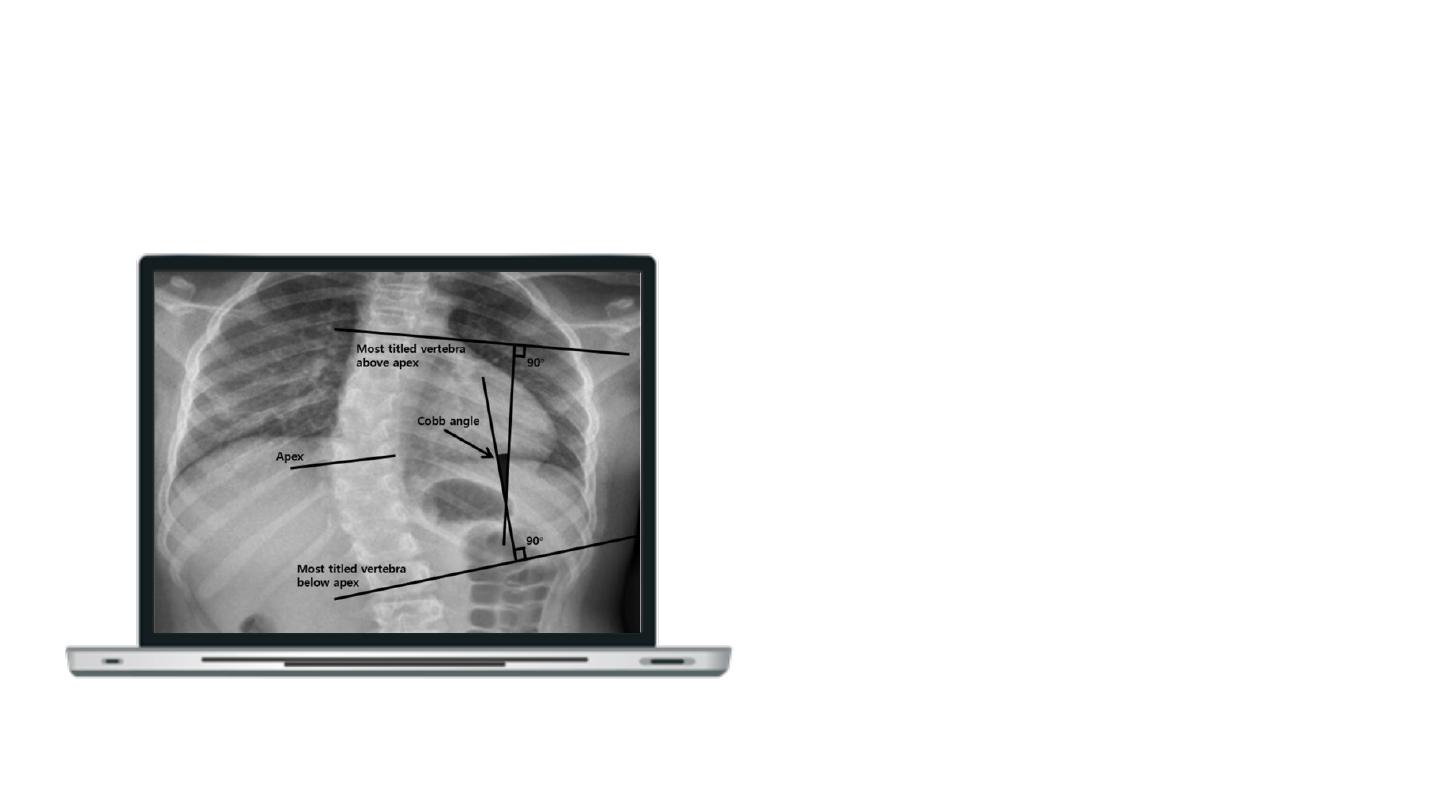

The Cobb Angle

The current golden standard for assessing spinal deformities.

1. Definition: the greatest angle at a particular

region of the vertebral column, when measured

from the superior endplate of a superior

vertebra to the inferior endplate of an inferior

vertebra.

2. Assessment: the Cobb Angles are preferably

measured while standing, and a person whose

Cobb Angle exceeds 10° will be diagnosed

scoliotic.

Measure the extent of lateral and

sagittal curvature of the spine based

on anterior-posterior (AP) and lateral

(LAT) X-ray images.

Cobb Angle Measurement

The Cobb Angle measurement.